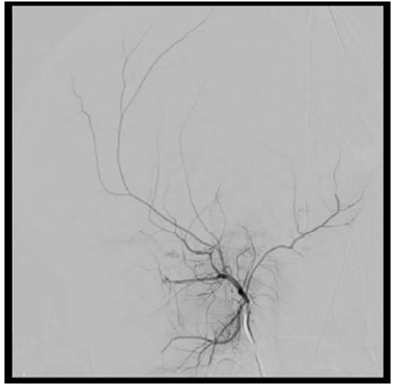

La arteriografía evidencia fístula carótido-cavernosa indirecta izquierda tipo D de la clasificación de Barrow. Presenta aferencias provenientes de la arteria carótida interna izquierda a través de un fino ramo corto carótido hipofisario, y de carótida externa izquierda a través de finos ramos de la arteria maxilar interna. El drenaje se produce hacia una vena oftálmica superior dilatada con flujo lento y hacia los senos petrosos (Figura 2yFigura 3).

Figura 2:Angiografía digital que muestra FCC indirecta izquierda tipo D de la clasificación de Barrow, alimentada por la arteria carótida interna izquierda a través un fino ramo corto carótido hipofisario. Seevidencia el drenaje hacia el seno cavernoso y de ahí a una dilatada vena oftálmica superior. A)Inyección por carótida interna izquierda, proyección lateral. B) Inyección por carótida interna izquierda, proyección frente. C) Inyección supraselectiva con microcateter desde el fino ramo carótido hipofisario.

Figura 3:Angiografía digital que muestra FCC indirecta izquierda tipo D de la clasificación de Barrow, alimentada por la arteria carótida externa izquierda a través de finos ramos de la arteria maxilar interna. Seevidencia el drenaje hacia el seno cavernoso y de ahí a una dilatada vena oftálmica superior.A) Inyección por carótida externa izquierda, proyección lateral. B) Inyección supraselectiva con microcateter desde un fino ramo de maxilar interna.